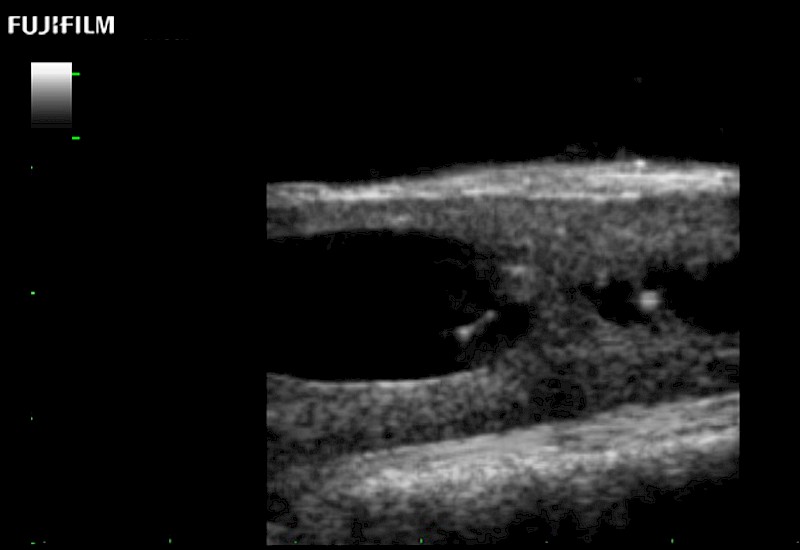

Extraordinary high-resolution digital imaging

Exceptional transducers

for use during: Cranial guidance, Burr-Hole guidance, Spinal Cord guidance, Pituitary guidance, Micro-Surgery guidance

Our dedication to neurosurgery allows us to offer superior image quality, outstanding system reliability and intuitive use of cutting edge technology.